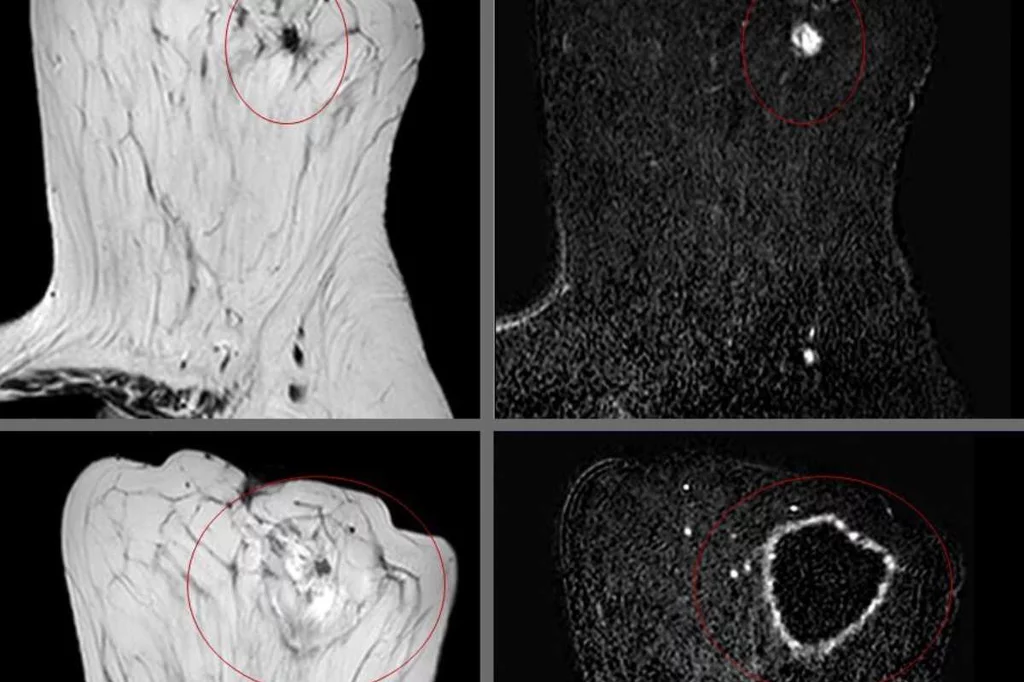

Para dar con el diagnóstico las pruebas son las mismas en adultos y menores. "Realizar una exploración neurológica sistematizada para identificar los signos caracterÃsticos de la misma y descartar signos que puedan hacer dudar", explica RodrÃguez de Rivera Garrido.

Además, Rivera añade como imprescindibles otras. "Una exploración neurofisiológica electromiográfica que debe revelar la afectación de las motoneuronas inferiores. Además de estudios de laboratorio y de neuroimagen a nivel craneal y medular, que descarten otros procesos subyacentes que pudieran explicar signos o sÃntomas similares", detalla. "Es muy importante asegurar el diagnóstico antes de confirmárselo a los pacientes, aunque conlleve una demora o la repetición de determinadas pruebas".